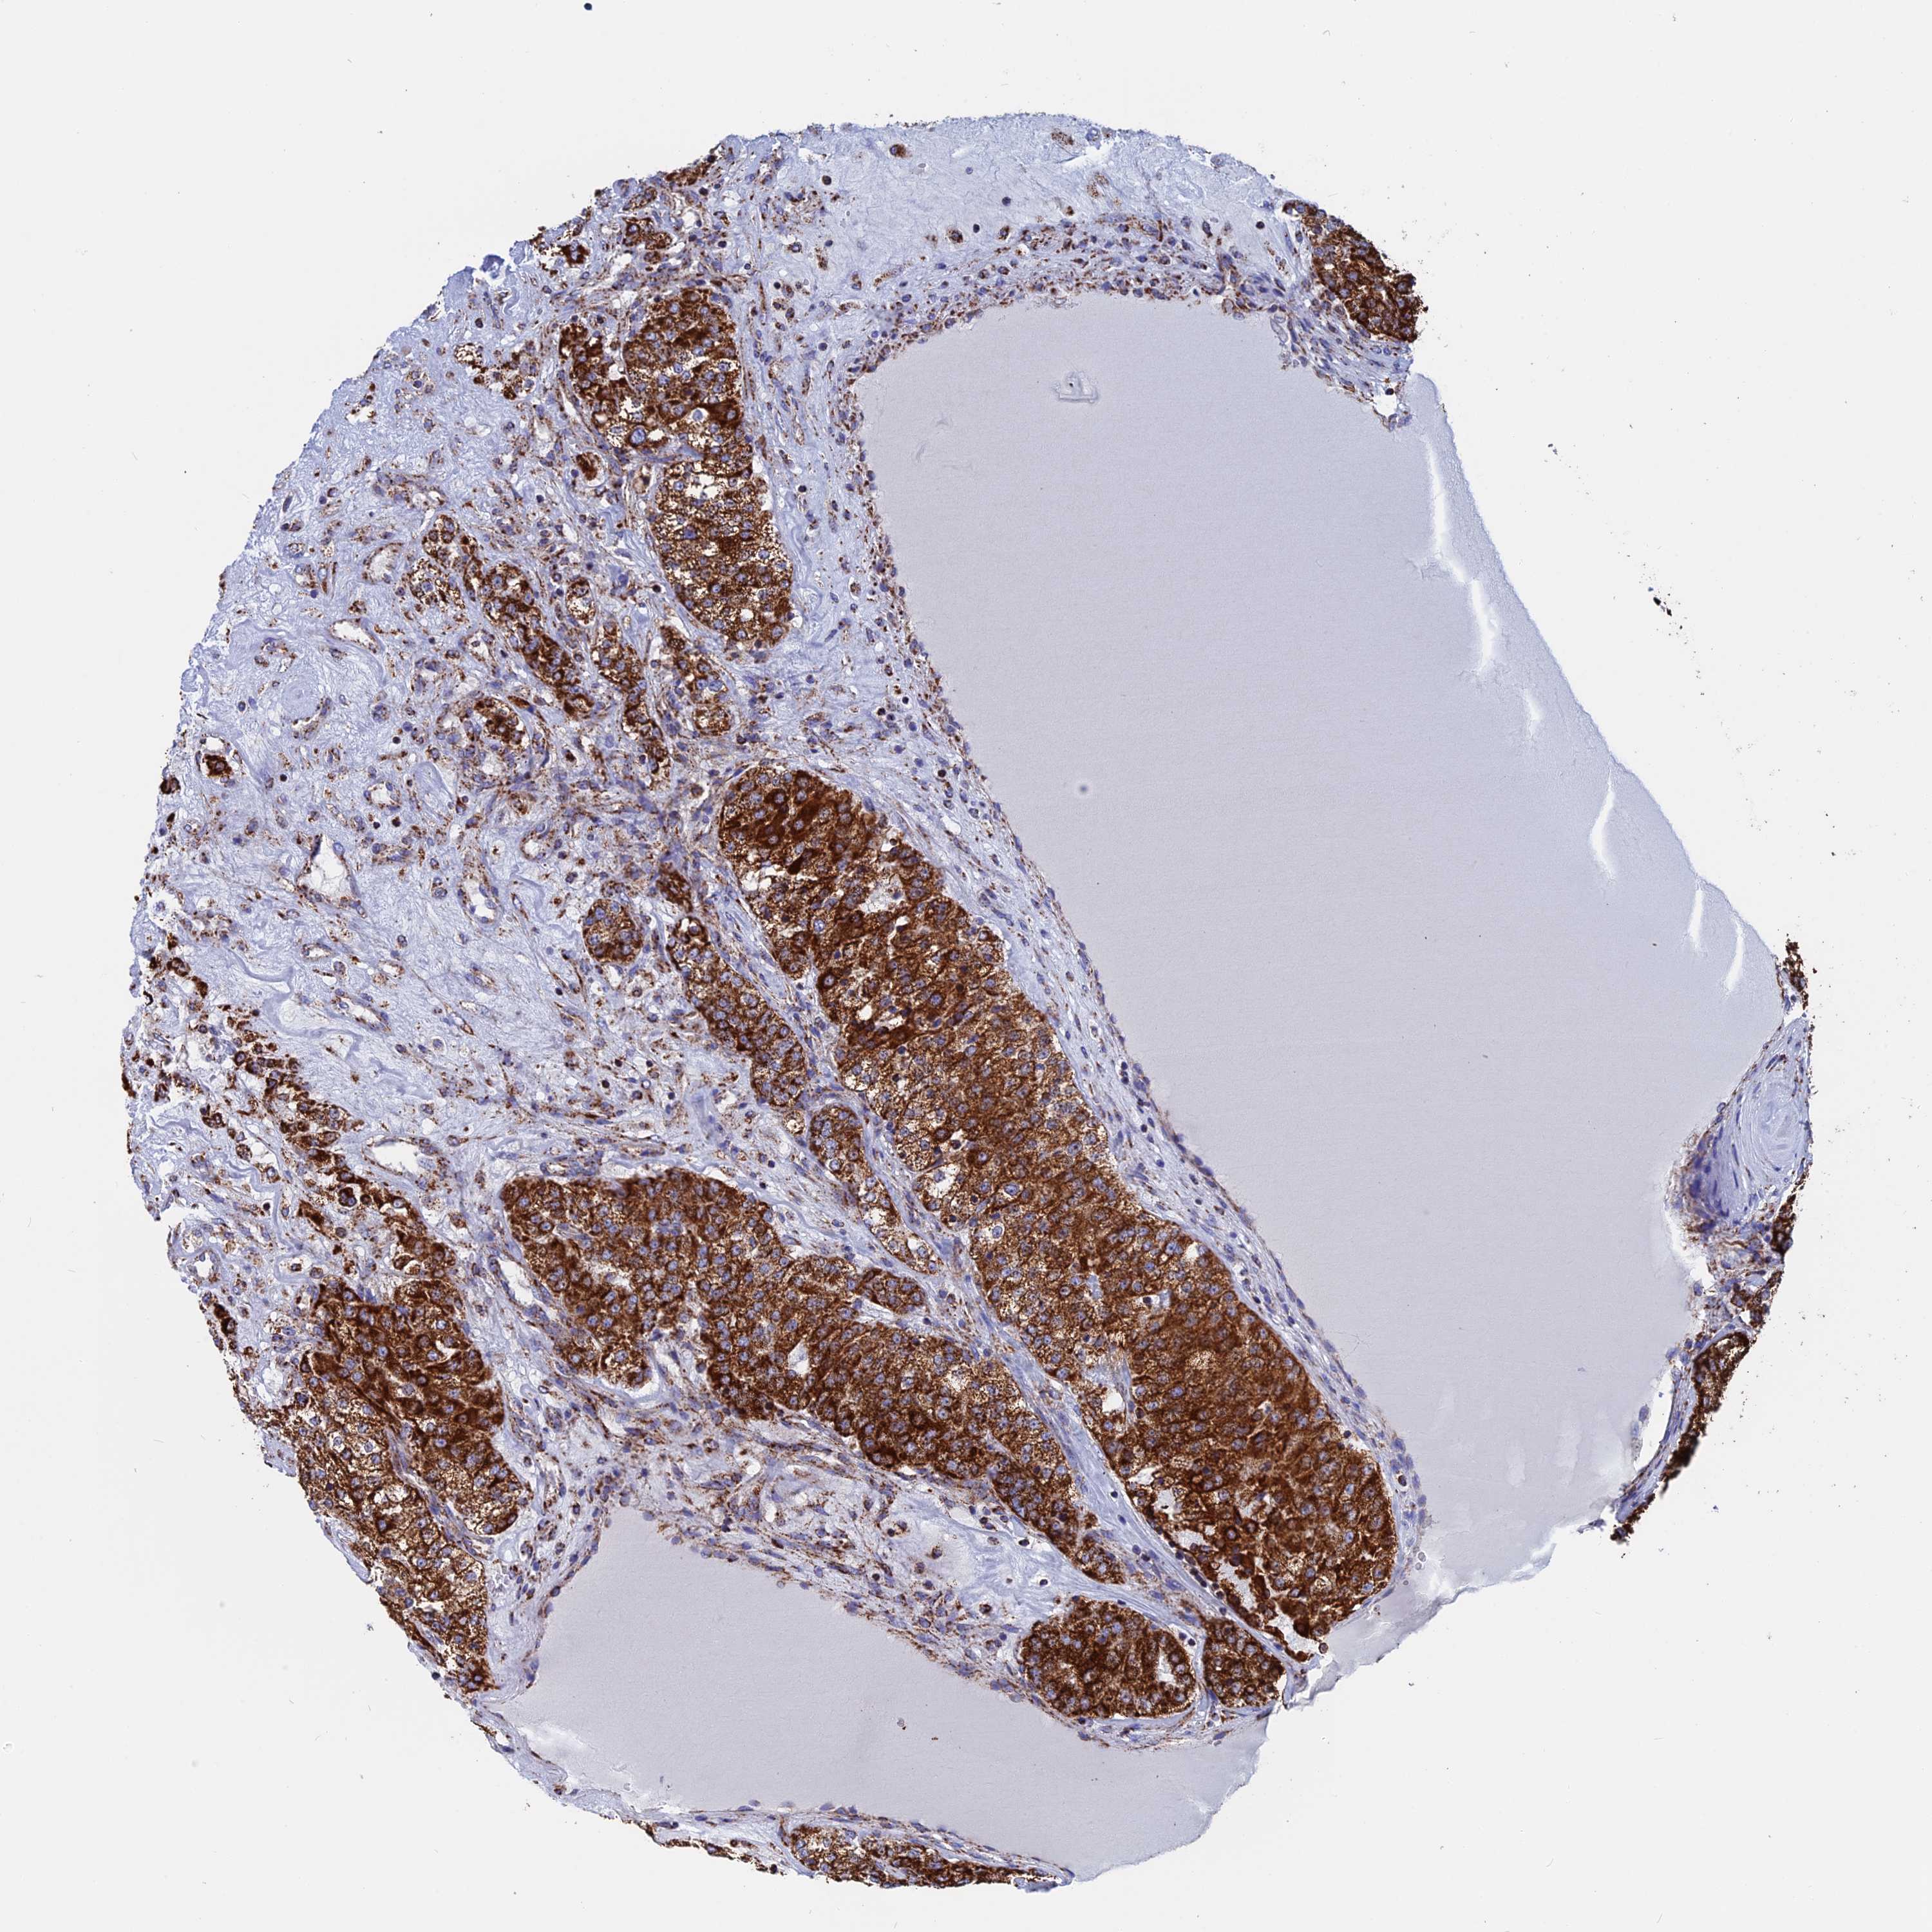

KIDNEY RENAL CLEAR CELL CARCINOMA (TCGA) - Interactive survival scatter ploti

The Survival Scatter plot shows the clinical status (i.e. dead or alive) for all individuals in the patient cohort, based on the same data that underlies the corresponding Kaplan-Meier plots. Patients that are alive at last time for follow-up are shown in blue and patients who have died during the study are shown in red.

The x-axis shows the expression levels (FPKM) of the investigated gene in the tumor tissue at the time of diagnosis. The y-axis shows the follow-up time after diagnosis (years). Both axes are complimented with kernel density curves demonstrating the data density over the axes. The top density plot shows the expression levels (FPKM) distribution among dead (red) and alive patients (blue). The right density plot shows the data density of the survived years of dead patients with high and low expression levels respectively, stratified using the cutoff indicated by the vertical dashed line through the Survival Scatter plot. This cutoff is automatically defined based on the FPKM cutoff that minimizes the p-score. The cutoff can be changed by dragging the vertical line or by entering a cutoff value in the square labeled "Current cut-off".

Under the Survival Scatter plot the p-score landscape (black curve; left axis) is shown together with dead median separation (red curve; right axis). Dead median separation is the difference in median mRNA expression between patients who have died with high and low expression, respectively. It is calculated as follows: median FPKM expression of dead patients with high expression - median FPKM expression of dead patients with low expression. This is intended to aid the user in visually exploring custom cutoffs and the associated p-scores and dead median separation.

Individual patient data is displayed and can be filtered by clicking on one or more of the category buttons on the top of the page. Categories describing expression level and patient information include: high, low, alive, dead, female, male and tumor stages. The scale of the x-axis can be toggled between linear and log-scale by clicking on the "x log" button. Mouse-over function shows TCGA ID, patient information and mRNA expression (FPKM) for each patient.

& Survival analysisi

Kaplan-Meier plots summarize results from analysis of correlation between mRNA expression level and patient survival. Patients were divided based on level of expression into one of the two groups "low" (under cut off) or "high" (over cut off). X-axis shows time for survival (years) and y-axis shows the probability of survival, where 1.0 corresponds to 100 percent.

WDR83 is potential prognostic, high expression is favorable in Kidney Renal Clear Cell Carcinoma (TCGA)

Best expression cut offi

Based on the FPKM value of each gene, patients were classified into two groups and association between prognosis (survival) and gene expression (FPKM) was examined. The best expression cut-off refers the FPKM value that yields maximal difference with regard to survival between the two groups at the lowest log-rank P-value. Best expression cut-off was selected based on survival analysis .

When clicking on this number, the vertical dashed line indicating cut-off, the interactive survival plot, and the Kaplan-Meier curve will be adjusted to show results based on the best expression cut-off.

: 6.05

TCGA RNA samplesi

RNA-seq data is reported as average FPKM (number Fragments Per Kilobase of exon per Million reads), generated by the The Cancer Genome Atlas (TCGA) .

Normal distribution across the dataset is visualized with box plots, shown as median and 25th and 75th percentiles. Points are displayed as outliers if they are above or below 1.5 times the interquartile range. FPKM values of the individual samples are presented next to the box plot.

Average pTPM 7.5

Number of samples 521